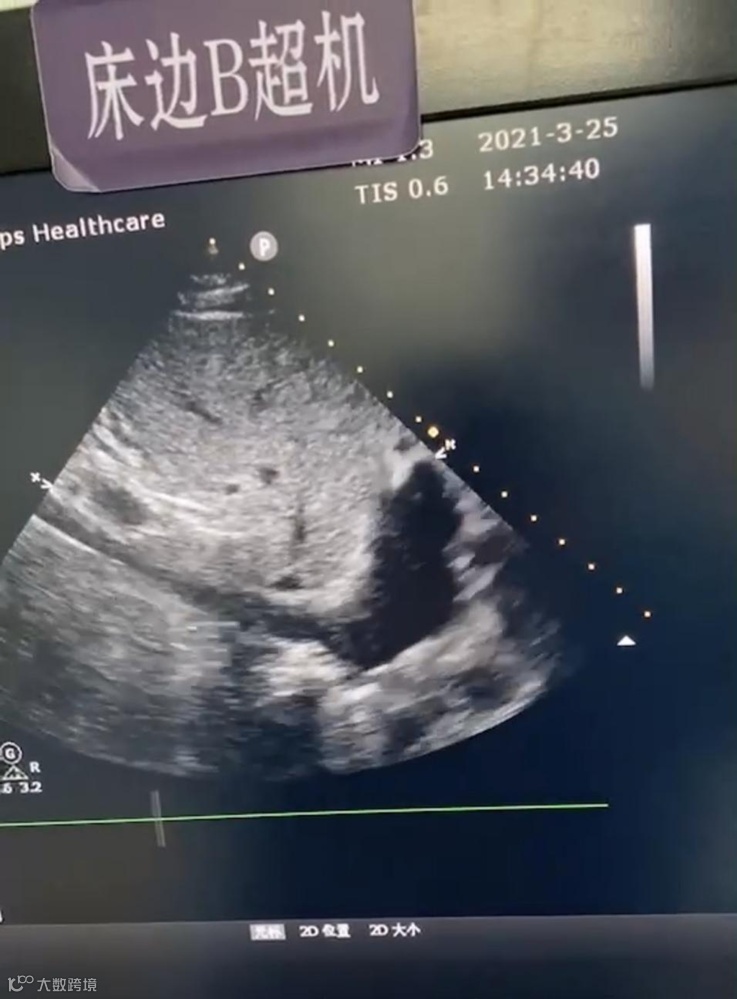

入院时床旁超声评估下腔静脉

经积极补液扩容后床旁超声评估下腔静脉